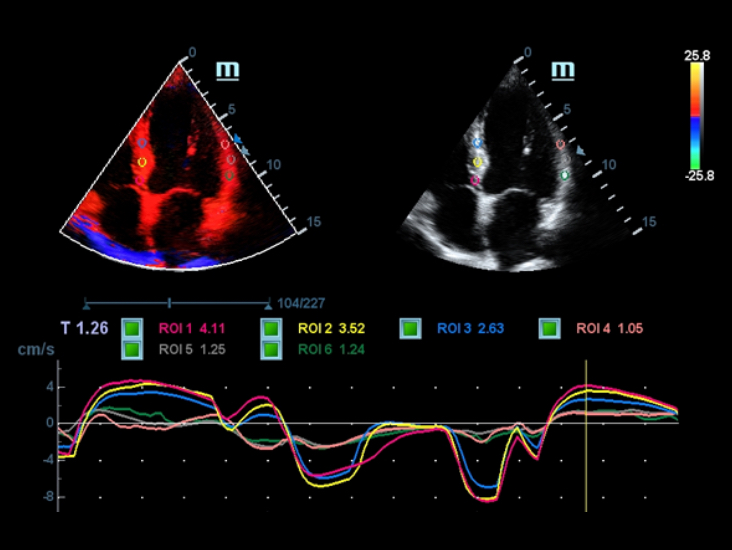

DC-40 con Full HD ofrece una gama de herramientas que maximizan la precisiĂłn del diagnĂłstico con comodidad. DC-40 con Full HD le brinda una soluciĂłn completa para aplicaciones clĂnicas convencionales, con un flujo de trabajo simplificado que garantiza la eficiencia y permite realizar escaneos generales, de ginecologĂa, obstetricia y cardiologĂa.